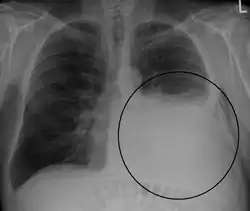

A large left-sided pleural effusion as seen on an upright chest X-ray

A pleural effusion is usually diagnosed on the basis of medical history and physical exam, and confirmed by a chest X-ray. Once accumulated fluid is more than 500 mL, there are usually detectable clinical signs, such as decreased movement of the chest on the affected side, dullness to percussion over the fluid, diminished breath sounds on the affected side, decreased vocal resonance and fremitus (though this is an inconsistent and unreliable sign), and pleural friction rub. Above the effusion, where the lung is compressed, there may be bronchial breathing sounds and egophony. A large effusion there may cause tracheal deviation away from the effusion. A systematic review (2009) published as part of the Rational Clinical Examination Series in the Journal of the American Medical Association showed that dullness to conventional percussion was most accurate for diagnosing pleural effusion (summary positive likelihood ratio, 8.7; 95% confidence interval, 2.2–33.8), while the absence of reduced tactile vocal fremitus made pleural effusion less likely (negative likelihood ratio, 0.21; 95% confidence interval, 0.12–0.37).[13]

A pleural effusion appears as an area of whiteness on a standard posteroanterior chest X-ray.[14] Normally, the space between the visceral pleura and the parietal pleura cannot be seen. A pleural effusion infiltrates the space between these layers. Because the pleural effusion has a density similar to water, it can be seen on radiographs. Since the effusion has greater density than the rest of the lung, it gravitates towards the lower portions of the pleural cavity. The pleural effusion behaves according to basic fluid dynamics, conforming to the shape of pleural space, which is determined by the lung and chest wall. If the pleural space contains both air and fluid, then an air-fluid level that is horizontal will be present, instead of conforming to the lung space.[15] Chest radiographs in the lateral decubitus position (with the patient lying on the side of the pleural effusion) are more sensitive and can detect as little as 50 mL of fluid. Between 250 and 600mL of fluid must be present before upright chest X-rays can detect a pleural effusion (e.g., blunted costophrenic angles).[16]